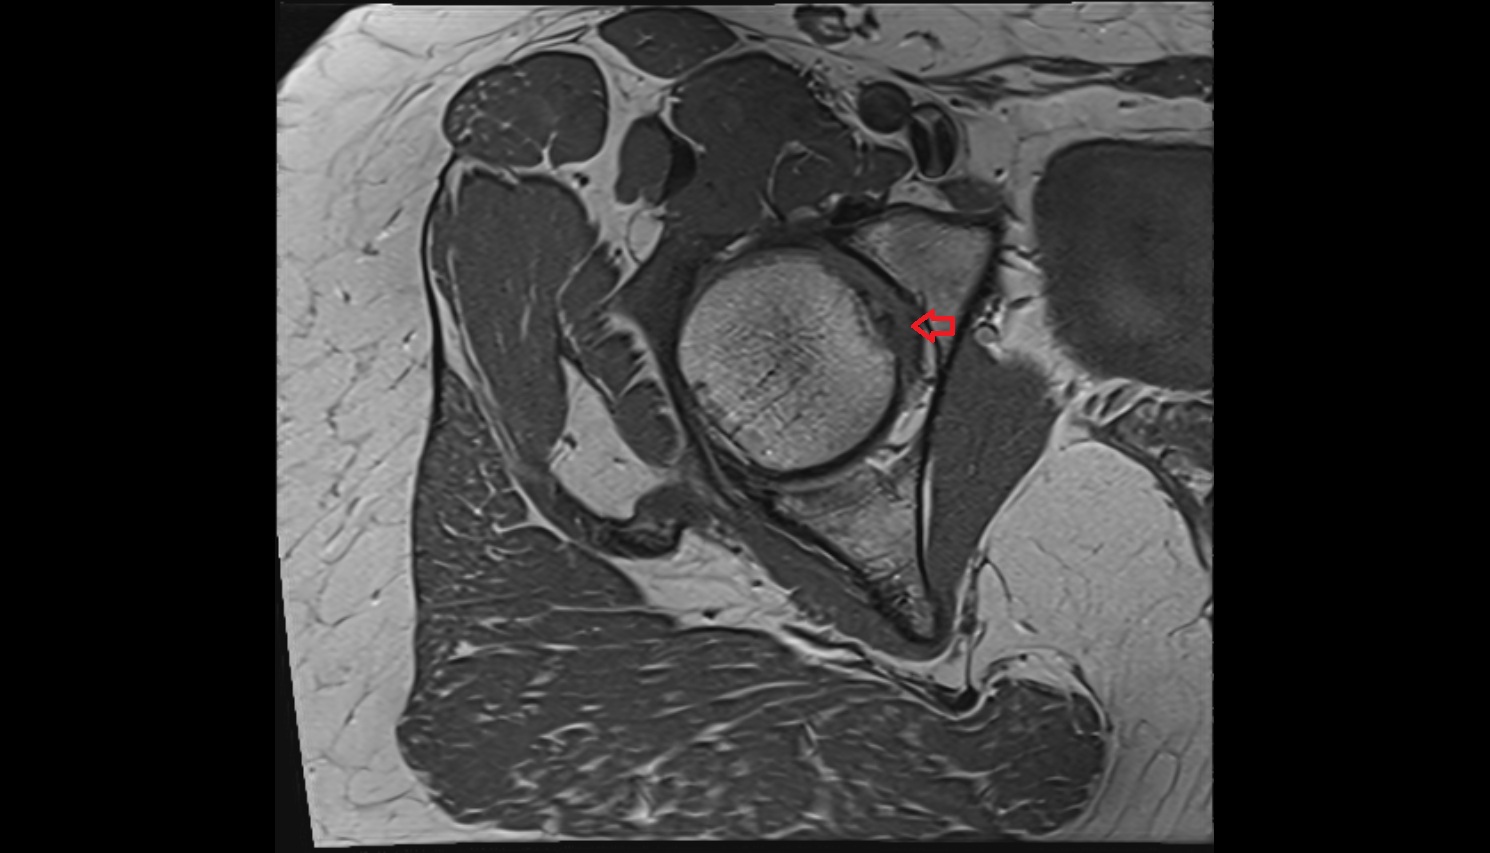

- Acetabular labrum

- Articular capsule of hip joint

- Hip joint